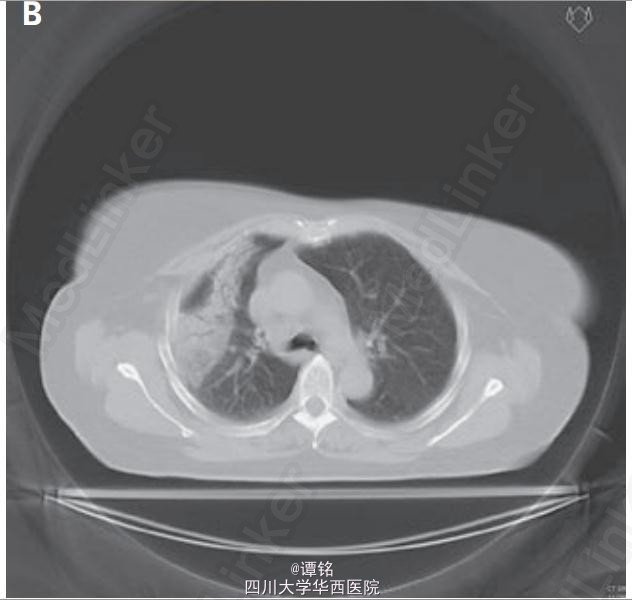

随后的CT扫描显示放射性肺炎的典型表现:包括非解剖性分布的实变(不与肺叶或支气管肺节段相对应)(图B),其中可见很多支气管气像,并伴有周围支气管轻度扩张,常可进展为牵拉性支气管扩张,尽管肺炎主要发生在肺的照射部位,但也可以播散至非照射区域。